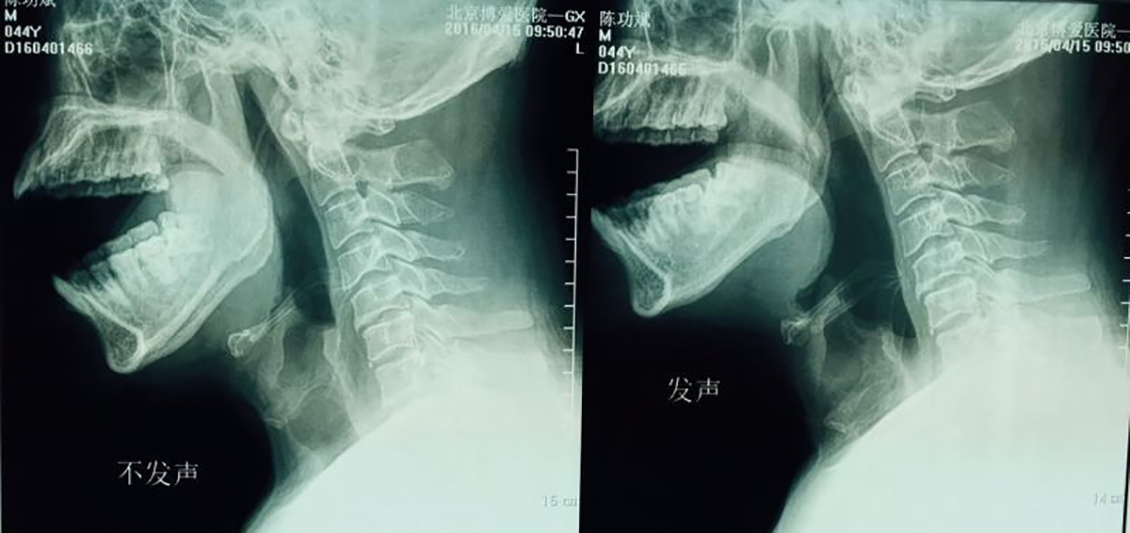

1、腭咽部侧位X线片

与语音密切相关的结构机制即功能机制的基础结构主要有软腭长度、咽腭深度、软腭落差、软腭动度角等,腭咽闭合功能是指在发音过程中软腭与咽后壁协调运动,在发某些音时软腭后1/3与咽壁形成广泛而紧密地接触,瞬间使口腔与鼻腔完全隔开,以维持语音的共鸣平衡,同时在口腔内形成一定的呼吸气流压力。

部分运动性构音障碍患者由于其上运动神经元损伤所致软腭上提乏力或不能,造成腭咽闭合功能不全即可确诊为腭咽闭合功能不全(velopharyngeal insufficiency,VPI)。

腭咽部侧位X线片是观察、分析软腭形态、运动的重要方法,可以测量静态和发声时软腭与咽后壁的距离评定软腭的上抬功能;评价运动性构音障碍鼻音化构音的程度,可以作为腭托(palatal lift prosthesis,PLP)制作和佩戴腭托后效果的评估。